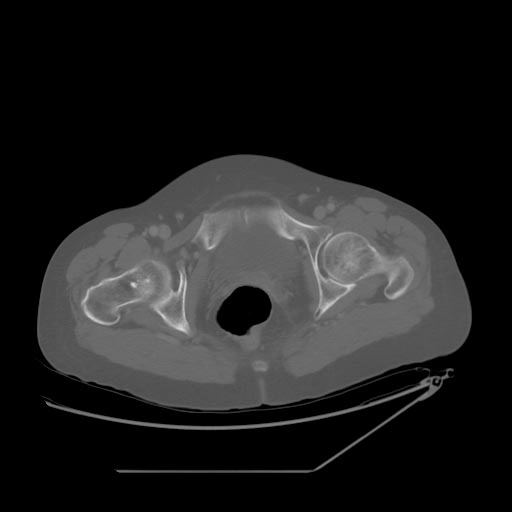

Nang xương phình mạch (Aneurysmal Bone Cyst - ABC)